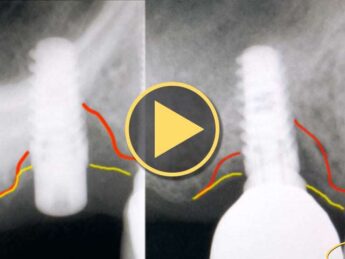

LightScalpel CO2 Laser Peri-Implantitis Treatment Results